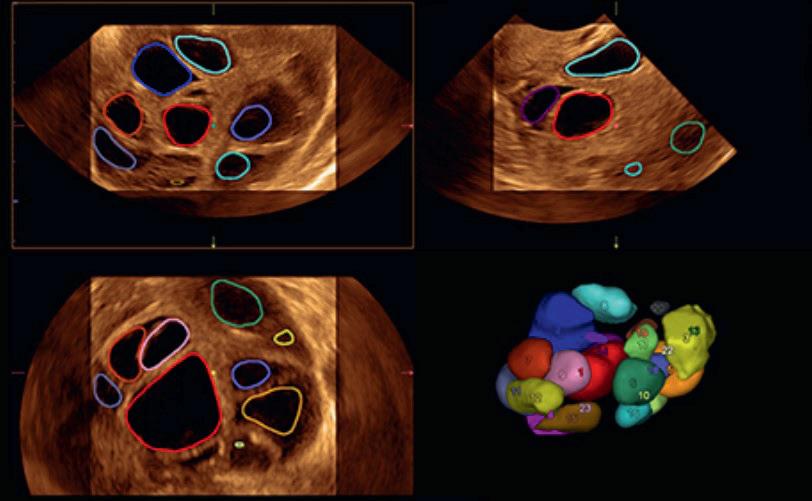

Våre erfaringer med hjemmeinduksjonsstudien er at dette bør være et alternativ til kvinnene som induseres, og vi har tatt metoden inn i vår lokale induksjonsprosedyre. Hos oss har vi gjort enkelte endringer etter studien, blant annet kan kvinner med vannavgang også få misoprostol hjemme. Ellers har vi økt til maks 8 tabletter i 2 påfølgende dager, men kvinnene kommer inn til sykehuset neste dag for å hente resterende 8 tabletter. På denne måten sparer vi tabletter som ikke blir brukt, og ikke minst får vi en kontakt med kvinnene slik at de lettere kan gi beskjed om problemer, spørsmål eller annet. Vi tar kun CTG før 1. dose misoprostol. Kvinnene som egner seg informeres om at de kan være hjemme, istedenfor at de informeres om at det er en mulighet å være hjemme. Alle får skriftlig informasjon om hvordan de skal ta tablettene hjemme og når de skal henvende seg til avdelingen. Flyten og den praktiske gjennomføringen av induksjonsstrømmen er vi således allerede i gang med å optimalisere.

Inntrykket vårt er at det å være hjemme i starten av induksjonen gi mer ro, komfort og trygghet totalt enn det vi kan tilby ved innleggelse, spesielt for flergangsfødende. Vi tror også at tabletter fremfor ballong kan være en enkel, skånsom og praktisk måte å bli indusert på, som både vi og kvinnene det gjelder vil trives med. Vi kommer gjerne tilbake med tall og resultater.

Fortsettelse følger!

25 Medlemsblad for Norsk Gynekologisk Forening

Kikhostevaksine

Gravide blir en målgruppe i barnevaksinasjonsprogrammet